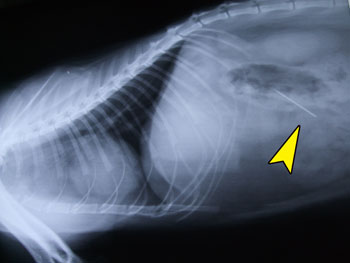

昨日の夕方のこと

「パッチワークしてたら”針”が1本足りないんです。

もしかして吉宗君(ネコ)が飲んじゃったのかも…」

!?工エエェ(゚〇゚ ;)ェエエ工!?

聞けば見ていたわけではない様で…

とにかくレントゲン検査です。

タンタン同様、皆で固唾を呑んで待ちました。

その結果は。。。。。。。

ありました。 _| ̄|●シクシク

緊急手術です。